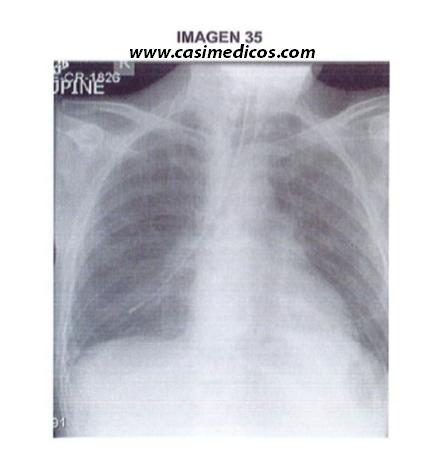

Pregunta nº 35 (vinculada a la imagen nº 35)

Está de guardia en planta de medicina y le avisan para comprobar si la sonda nasogástrica (SNG) se encuentra situada correctamente antes de iniciar una nutríciún enteral. Tras examinar la radiografía de tórax (imagen), ¿cuál debe ser la actitud a seguir?

- Retirar la SNG y volverla a introducir.

- Conectar una jeringa a la sonda e insuflar 10-20 cc de aire mientras. escucho ruidos en el estómago con el fonendoscopio.

- Iniciar la nutrición enteral ya que la SNG está en posición correcta.

- Progresar la SNG cuatro centímetros más.ç

Respuesta correcta: 1.

En la radiografía de tórax se comprueba que la SNG se desvía hacia el bronquio principal derecho, por lo que de las opciones que nos presentan, la única correcta y razonable es retirarla y volverla a introducir.